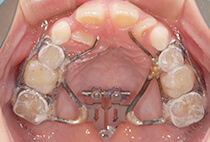

診断の結果は、以下が原因の骨格性反対咬合。

反対咬合でよくあるケースです。

治療方法は、小さな上顎の成長誘導。

急速拡大装置と前方けん引装置を使用します。